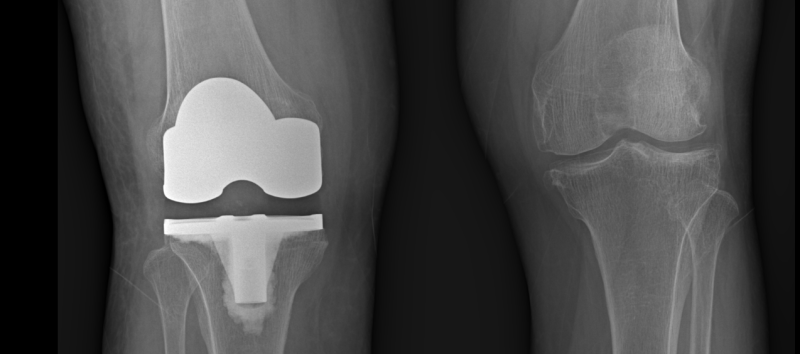

무릎관절도 하중을 견디는 관절로 운동범위가 넓기 때문에 관절 사이에 반월상연골이라는 연골이 있어 관절이 자유롭게 움직일 수 있습니다. 나이가 들면 무릎 관절이 변형되고 연골이 손상됩니다. 관절경은 또한 손상된 연골을 복구하는 데 사용됩니다. 변형이 어느 정도 이상으로 심할 경우 관절 자체를 대체하는 인공관절 수술을 시행합니다.

관절 치환술은 슬관절의 수컷 관절인 경골-대퇴 관절을 새로운 관절로 교체하는 것으로 수술량이 비교적 많고 회복 시간이 오래 걸린다. 많은 경우 수술이 끝난 것처럼 보이지만 새로운 인공구조물이 기존 조직에 잘 이식되어야 하고 외과적으로 절개된 피부나 근육 등의 연조직은 회복하는 데 시간이 걸립니다. 또한 수술 후 휴식을 취하는 동안에는 주변 근육의 부피가 줄어들고 근력이 저하되기 때문에 근력 운동도 필요하다.